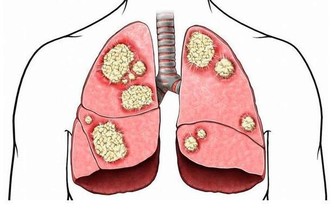

肝臟是人體中排毒解毒的重要器官,也是人體中最大的消化器官,生活中許多肝病患者是由於過度飲酒導致的,過度飲酒會增加肝臟以及腸胃的負擔,肝臟在人體內非常脆弱,起初患肝病,人體並沒有明顯症狀,因此,很多人錯過了治療肝臟最佳時期,當肝臟疼痛的時候,往往代表肝臟已經受損嚴重,生活中我們應該及時發現身體不適,定期去醫院做檢查,及時發現,及早治療。